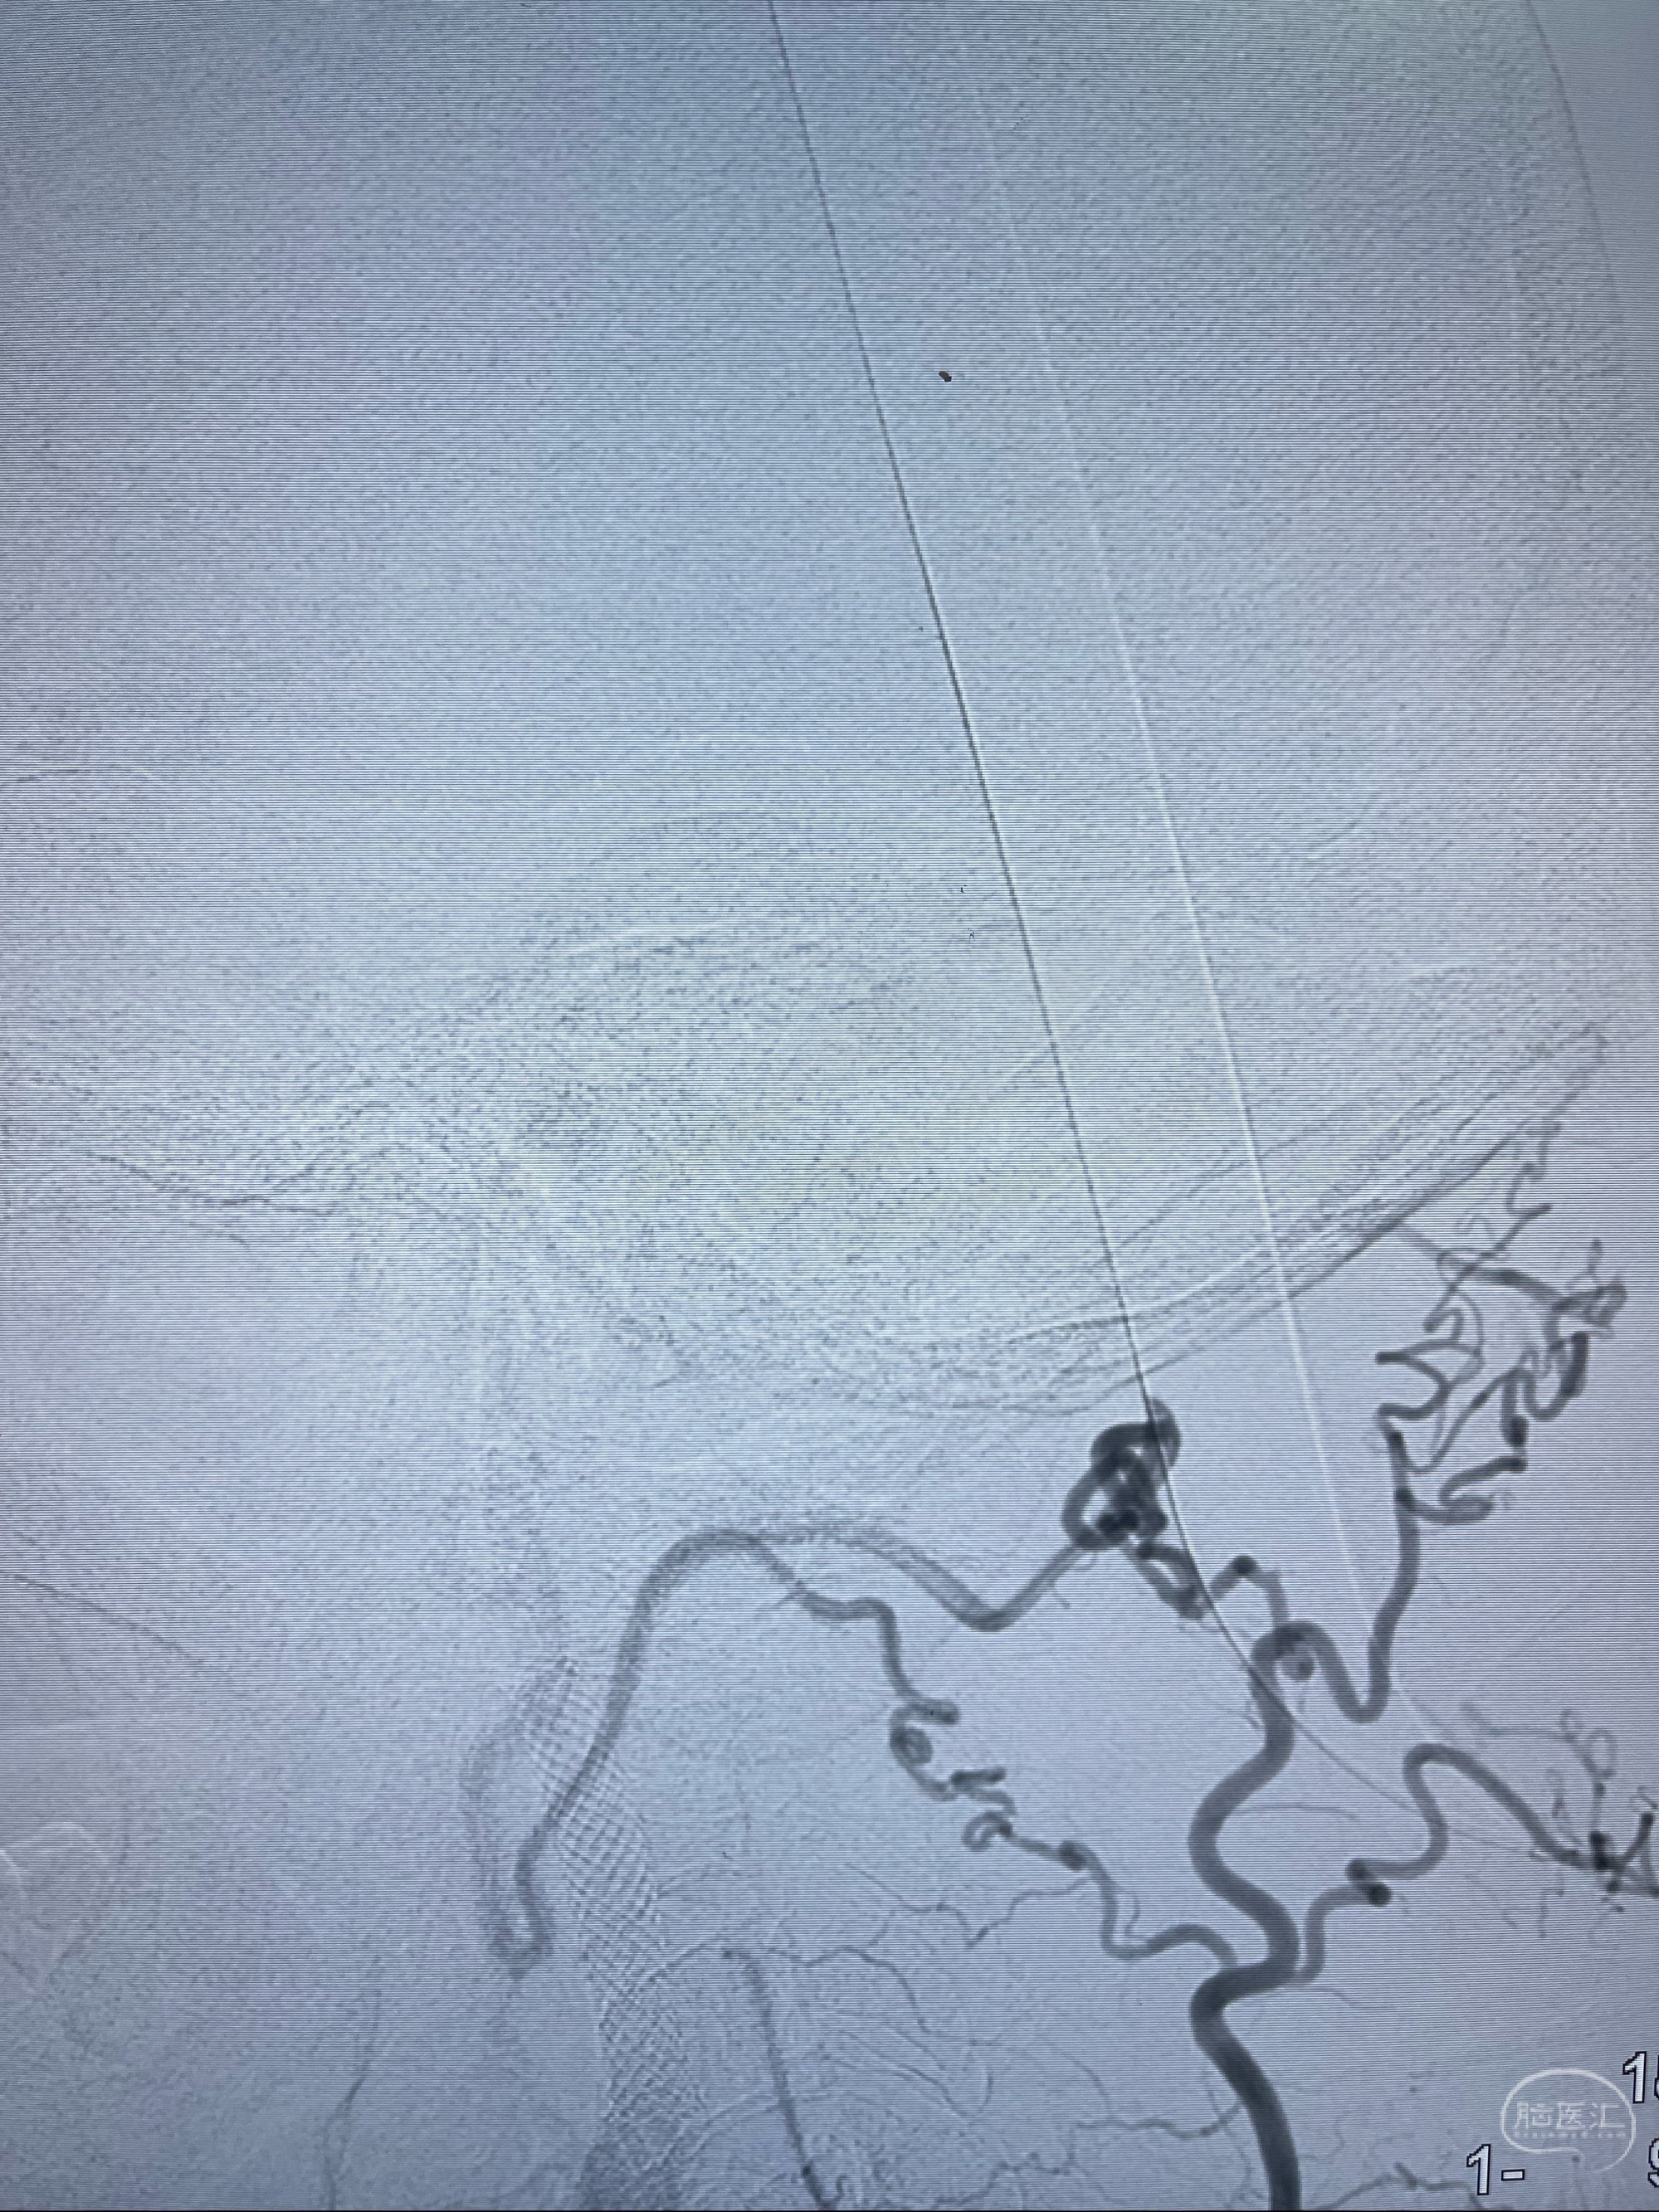

2023-07-10DSA:右侧颈内动脉岩骨段夹层伴中偏重度狭窄改变,左侧颈总动脉闭塞、右侧颈外动脉由右侧肋颈干甲颈干吻合代偿

箭头所示为颈内动脉岩骨段重度狭窄,结合MRI,考虑为肿瘤侵犯右侧颈内动脉

箭头以近至支架段管腔不规则狭窄

经导引导管造影显示支架远端颈内动脉不规则狭窄伴局部充盈缺损,同时行全身肝素化5ml